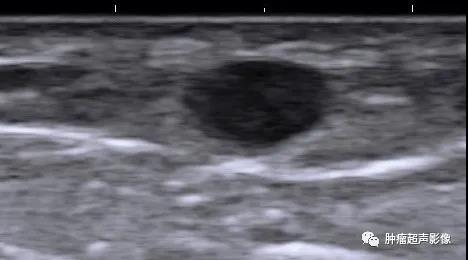

血管平滑肌瘤是位于皮下或真皮深部的良性肿瘤,由血管及平滑肌构成,肿瘤内成熟的平滑肌束位于血管周围或穿插分布于血管之间,虽然肿瘤内血管明显,但管腔通常...

血管瘤是血管畸形形成的肿块,可能累及皮肤或内脏,肝脏比较常见。肝血...